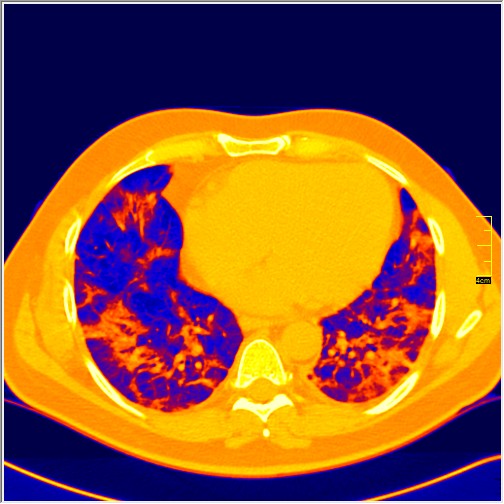

Foto: Aleksandar Ivković Foto: Aleksandar Ivković Foto: Aleksandar Ivković Strašna razlika kod pluća pušača i kovid pozitivne osobe autor: Božica Luković Zdravlje 23. jan. 2021. 12:06 > 23. jan. 2021. 12:15 0 Podeli vest: Radiolog Aleksandar Ivković od početka pandemije daje korisne informacije o svim aspektima kovida 19. On je nedavno uporedio rendgen snimke pluća zdrave osobe, pušača, osobe koja je zaražena gripom H1N1, a onda i osobe koja ima kovid 19. Razlike su zapanjujuće. Podeli vest: Oglas Objavu doktora Ivkovića sa njegovog bloga "Ljudi i ostale laži" prenosimo u celosti."Nedavno sam video u medijima da je neko preneo rdg sliku i razlike kod nalaza zdrave osobe, pušača i bolesnog od kovida 19. Kako nisam baš previše zadovoljan onim što je prikazano, evo kako to izgleda u našoj varijanti. Zdrava osoba CT nalaz kod zdrave osobe podrazumeva da ne postoje nikakvi poremećaji strukture plućnog parenhima, da su krvni sudovi uredni i da nema suženja disajnih puteva, kao i da nema uvećanih limfnih žlezda u hilusima pluća i medijastinumu. Foto: Aleksandar Ivković | Foto: Aleksandar Ivković * Foto: Aleksandar Ivković | Foto: Aleksandar Ivković Zdrava muška osoba mesec dana nakon zapaljenja pluća tokom kovida 19. Nalaz bez nekih posebnih problema iako se naziru tragovi zapaljenja. Snimak u boji je zdrava osoba, nepušač, bez ikakvih bolesti pluća u istoriji. Grip H1N1 Pokazaću samo drastične nalaze kod gripa H1N1, to je znači onaj grip koji je izazvao epidemiju španske groznice i epidemiju 2009. godine koja još uvek nije prestala (svake godine imamo makar 15%). Foto: Aleksandar Ivković | Foto: Aleksandar Ivković * Foto: Aleksandar Ivković | Foto: Aleksandar Ivković * Foto: Aleksandar Ivković | Foto: Aleksandar Ivković * Foto: Aleksandar Ivković | Foto: Aleksandar Ivković Nisu svi pacijenti imali ovakve nalaze, pokazujem one koji su imali tešku kliničku sliku. Kod gripa se sve odvija obično u sedam dana. Kao što se vidi, zapaljenje je bilo jednostrano, uglavnom. Ali kada je dolazilo do pogoršanja, onda je centralno obostrano dolazilo do edema pluća. Pušenje Kod pušača postoje razne varijante nalaza na plućima. U principu nisu tako dramatične kao što su zapaljenja. Nalaz na plućima kod pušača može biti potpuno normalan. Ovo ne pišem zato što podržavam pušenje, naprotiv, veliki sam protivnik, ali iznošenje laži nikada nije dobro. Dve dijagnoze su bitne kao posledica pušenja. Prva je hronična plućna opstruktivna bolest: Foto: Aleksandar Ivković | Foto: Aleksandar Ivković * Foto: Aleksandar Ivković | Foto: Aleksandar Ivković * Foto: Aleksandar Ivković | Foto: Aleksandar Ivković Jasna je razlika u nalazu, posebno na ovim slikama u boji, gde su ta plava polja delovi pluća koji su propali zbog cigareta (može da se uporedi sa zdravim plućima iznad).Druga bolest koja je česta kod pušača je u svakom slučaju karcinom. Foto: Aleksandar Ivković | Foto: Aleksandar Ivković * Foto: Aleksandar Ivković | Foto: Aleksandar Ivković * Foto: Aleksandar Ivković | Foto: Aleksandar Ivković * Foto: Aleksandar Ivković | Foto: Aleksandar Ivković Tkivo koje raste unutar pluća i razjeda ga. Takav je nalaz kod karcinoma pluća. Često je uzrok upotreba cigareta. Kovid 19 O kovidu sam pisao puno puta. Evo nekih slika, radi poređenja. Foto: Aleksandar Ivković | Foto: Aleksandar Ivković * Foto: Aleksandar Ivković | Foto: Aleksandar Ivković * Foto: Aleksandar Ivković | Foto: Aleksandar Ivković * Foto: Aleksandar Ivković | Foto: Aleksandar Ivković Nakon što pacijent bude izlečen od gripa ili kovida 19, pluća se mogu vratiti u normalu.To je razlika u odnosu na posledice upotrebe cigareta. Ovi snimci nisu postavljeni da bi se poredile bolesti, već da bi se ukazalo kako različite bolesti deluju na pluća. I ono što je veoma važno, ako neko dobije jednu od ovih bolesti, ne znači da u toku života neće dobiti drugu.Ne pišem zato smo smatram da sam najpametniji ili najpozvaniji da objašnjavam, nisam kao neki pojedinci ubeđen da samo ja imam znanje i istinu, pišem jer drugi ćute. Pišem jer ima i puno onih koji iznose laži, mora se tome stati na put.A ovi, koji pišu da sam umro, da sam oboleo od karcinoma, ovi koji mi žele da nađem dobro grobno mesto, šta da vam kažem, vi ste mi inspiracija. Svesni ste da sam u pravu i odlično znam da ste već uradili sve da se vakcinišete i mnogi od vas će to uraditi pre mene ali i dalje ćete ubeđivati druge da se ne vakcinišu i da je dobro za njih da se razbole i umru. Ima puno reči za vas u svim našim slovenskim jezicima, znate vi sami šta ste", piše dr Ivković.***Bonus video:https://youtu.be/MWucTT0qBsIPratite nas i na društvenim mrežama:FacebookTwitterInstagram Dr Lukić otkrio spisak svih antibiotika za kovid upalu pluća Zdravlje 0 Dr Žujović: Kako oporaviti pluća posle korone Zdravlje 0 Pet znakova da ti je kovid zahvatio pluća Zdravlje 0 Virusolog Ana Banko ruši veliku zabludu o ruskoj vakcini Emisije 0 aleksandar ivković korona kovid pluća snimak pluća Pratite nas na društvenim mrežama: Koje je tvoje mišljenje o ovoj temi? Učestvuj u diskusiji ili pročitaj komentare Budite prvi koji će ostaviti komentar Pošalji komentar Pročitaj komentare (0)